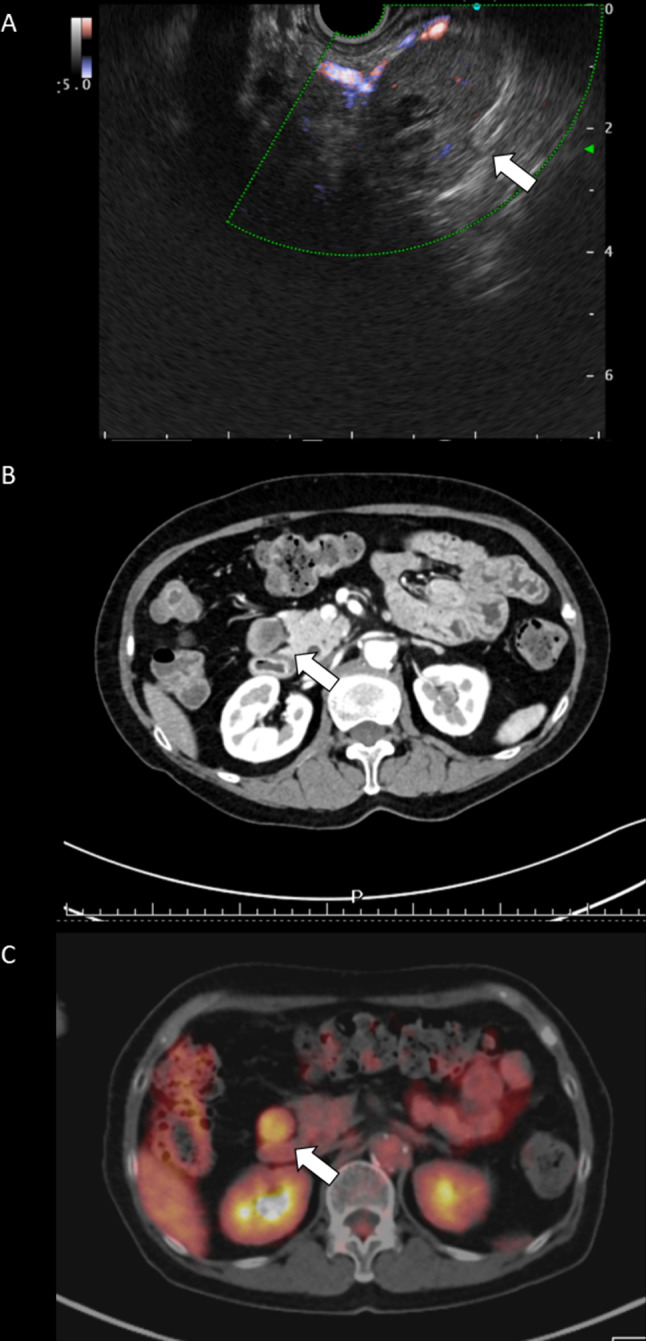

Fig. 2.

Preoperative examination. A Endoscopic ultrasonography findings showing the tumor of pancreas head to be well-circumscribed, hypoechoic with partially cystic change and hypovascular Doppler signaling. B Enhanced abdominal computed tomography (CT) findings showing an oval and poor-enhanced mass in front of the right kidney. C Planar and single photon emission computed tomography (SPECT) & maximum intensity projection (MIP) findings showing abnormal uptake in the pancreas head